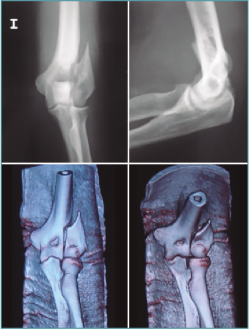

Las fracturas que se presentan con una mínima inflamación son susceptibles de fijación artroscópica asistida. El hematoma y los restos articulares se eliminarán y usaremos una o varias AK para reducir la fractura percutáneamente (Figuras 9 a 12) colocando a continuación tornillos canulados en la columnas medial o lateral del húmero. Se debe usar el fluoroscopio para evitar introducirlo dentro de la fosa olecraniana(11).

Figura 9. Radiografías y tomografía axial computarizada de fractura supraintercondílea.

Figura 10. Colocación del paciente, visión articular de la fractura y reducción artroscópica.

Figura 11. Fijación interna con 3 tornillos canulados, control por escopia y artroscópica.

Figura 12. Resultado final.